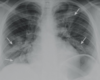

Estudios de imagen en COVID-19

Rx útil en seguimiento, poco sensible al inicio * Hallazgos similares a cualquier neumonía viral * Consolidación en vidrio despulido *Patrón reticular TC mayor sensibilidad + Consolidación periféricas en vidrio esmerilado

COVID-19 con patrón de vidrios despulido

COVID-19 con patrón en vidrio despulido

Vidrio despulido